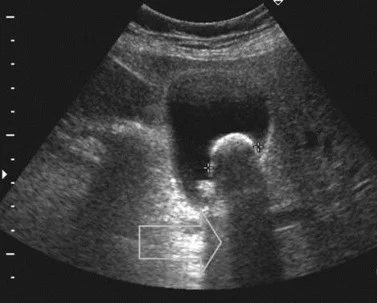

• Extended Focused Abdominal Sonography in Trauma (eFAST)

• Abdominal Aorta Sonography